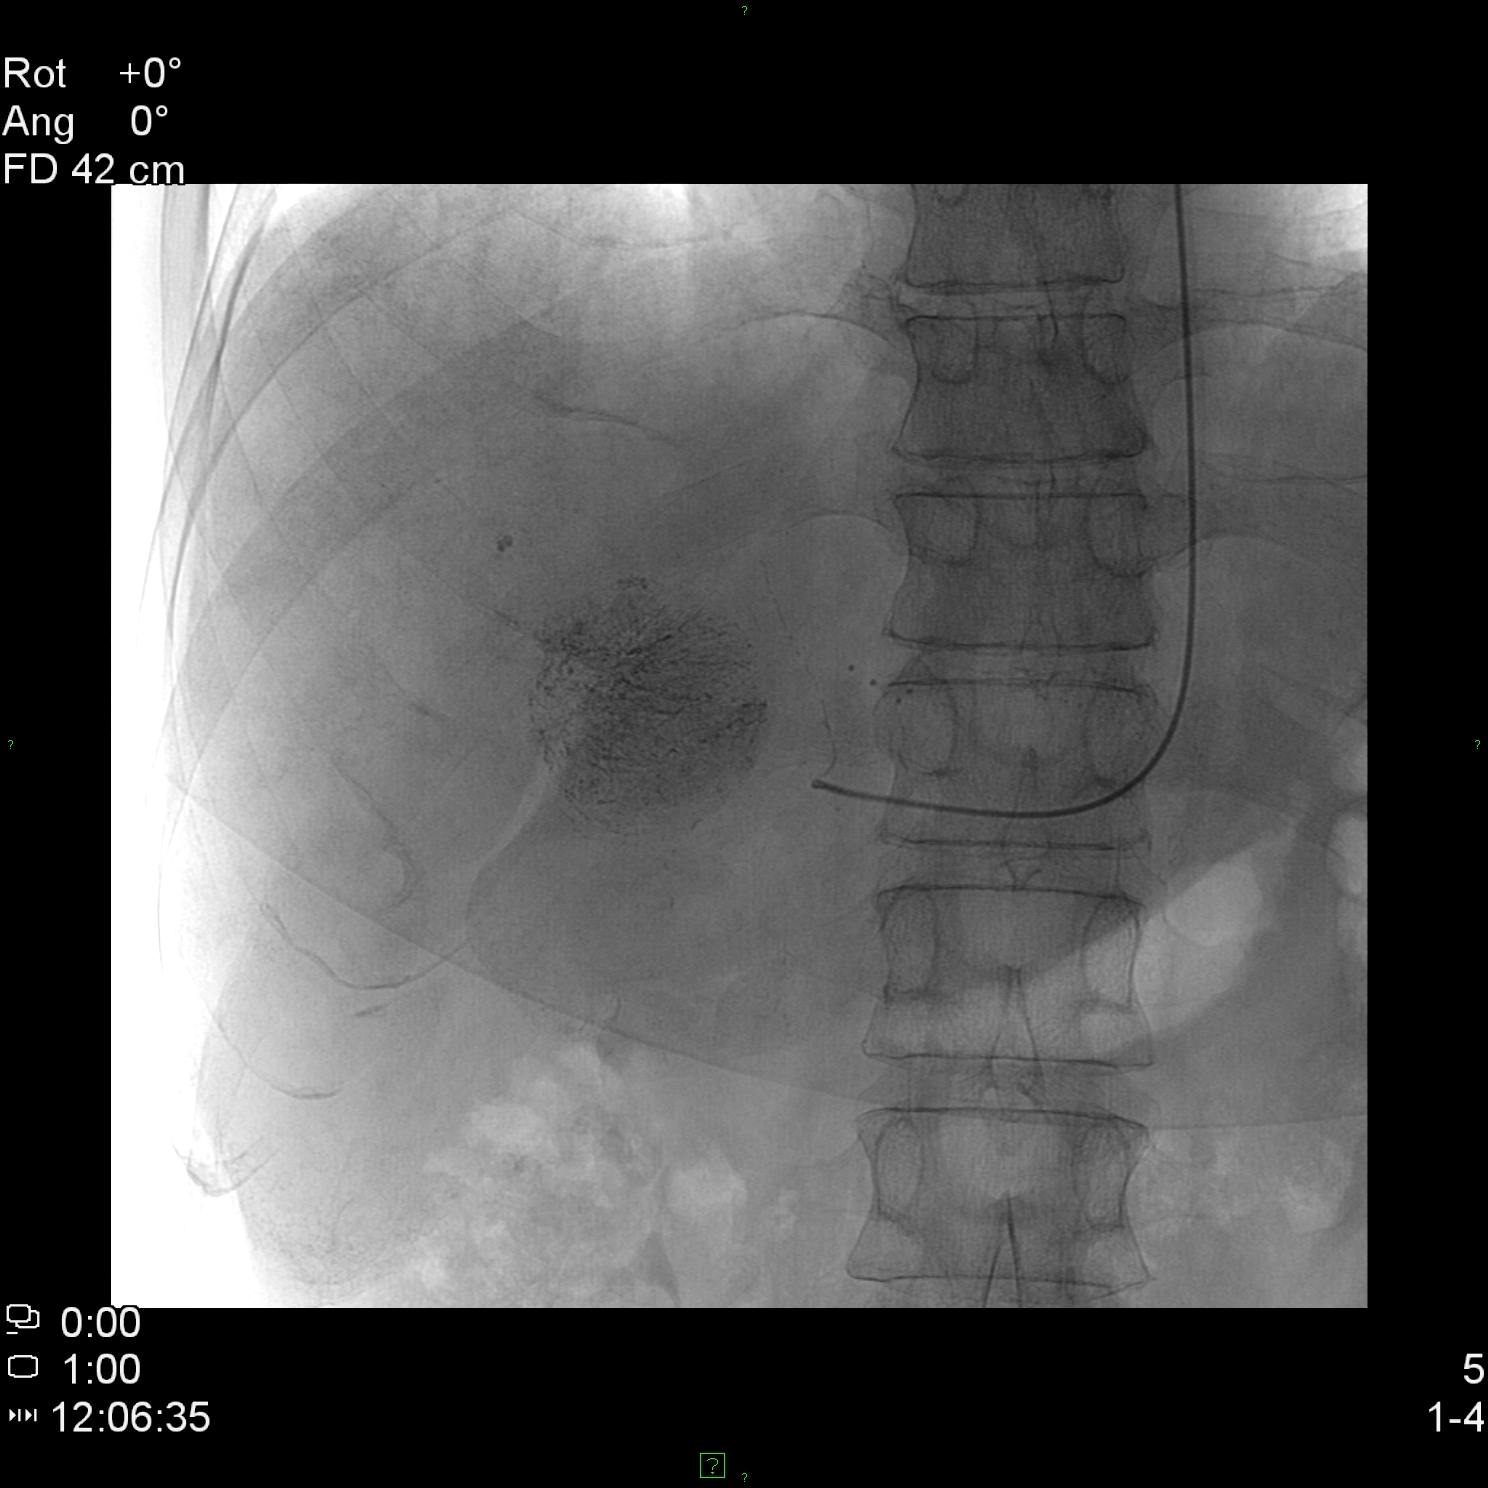

The CT-angiography and MR-angiography methods take nowadays over from the diagnostic selective catether hepatic angiographies. The catheter angiographies are performed in case of therapeutic (TAE – Figure 7, TACE, chemoperfusion) interventions and the traumatic liver injuries (selective embolisation) on these fields.

Figure 7: TAE (Transarterial Embolisation) of the liver with Lipiodol